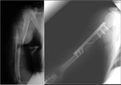

Kolda doku zedelenmesi yaşadıktan sonra ne yapmalıyım? Morarma ve şişlik oluştu, bu normal mi? Ayrıca, bu tür bir zedelenmenin iyileşme süresi ne kadar sürer? Spor yaparken bu durumdan nasıl korunabilirim? Tecrübelerinizle yardımcı olursanız sevinirim.

Kolda Doku Zedelenmesi Sonrası Yapılması Gerekenler

Eğer kolda doku zedelenmesi yaşadıysanız, öncelikle bölgeyi dinlendirmelisiniz. Morarma ve şişlik normal bir tepki olabilir, ancak bu belirtiler şiddetliyse bir sağlık profesyoneline danışmanızda fayda var.

Spor Yaparken Korunma Yöntemleri

Spor yaparken korunmak için ısınma hareketlerini atlamamalı, uygun ekipman kullanmalı ve tekniklerinizi doğru bir şekilde uygulamalısınız. Ayrıca, aşırı zorlamalardan kaçınmak önemlidir.